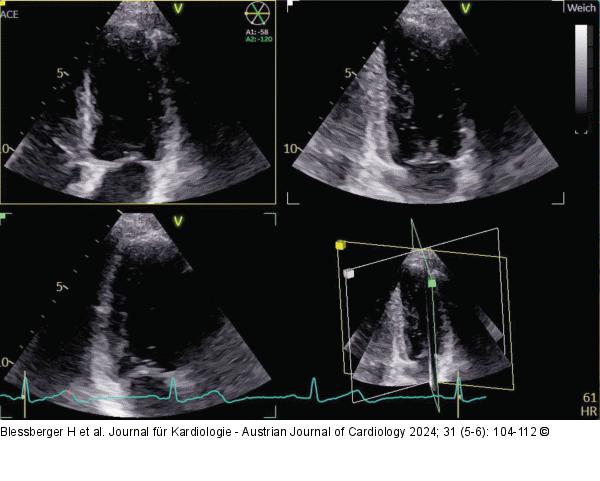

Abbildung 2: Echo Triplane Aufnahme des linken Ventrikels mit einem 3D-Schallkopf (apikaler 4-Kammer-Blick links oben, 2-Kammer-Blick rechts oben, 3-Kammer-Blick links unten). |

Triplane Aufnahme des linken Ventrikels mit einem 3D-Schallkopf (apikaler 4-Kammer-Blick links oben, 2-Kammer-Blick rechts oben, 3-Kammer-Blick links unten). |